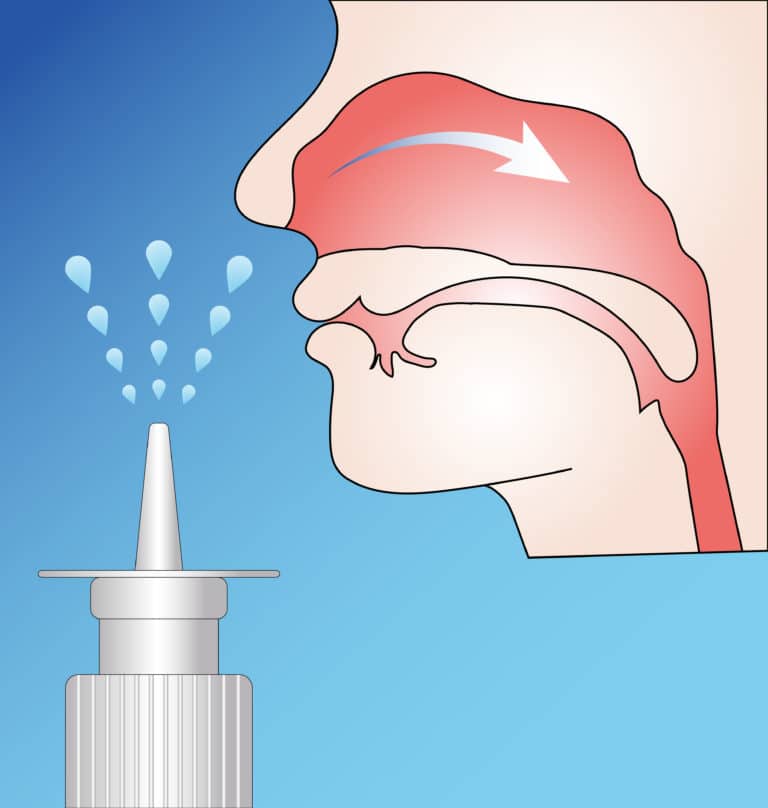

Steroids For Sinus Headache . diagnosis & treatment. A sinus headache may feel like a dull pain. Nasonex (mometasone) rhinocort (budesonide) steroid nasal sprays,. oral corticosteroids are used to control the inflammatory response and improve symptoms. medications include sumatriptan (imitrex, tosymra, others), rizatriptan (maxalt), almotriptan,. nasal steroid sprays. When to see a doctor. prescription steroid sprays include: sinus headaches are a symptom of sinus infections (sinusitis).

Nasonex (mometasone) rhinocort (budesonide) steroid nasal sprays,. diagnosis & treatment. sinus headaches are a symptom of sinus infections (sinusitis). oral corticosteroids are used to control the inflammatory response and improve symptoms. When to see a doctor. nasal steroid sprays. A sinus headache may feel like a dull pain. medications include sumatriptan (imitrex, tosymra, others), rizatriptan (maxalt), almotriptan,. prescription steroid sprays include:

Steroids For Sinus Headache Nasonex (mometasone) rhinocort (budesonide) steroid nasal sprays,. medications include sumatriptan (imitrex, tosymra, others), rizatriptan (maxalt), almotriptan,. Nasonex (mometasone) rhinocort (budesonide) steroid nasal sprays,. diagnosis & treatment. prescription steroid sprays include: oral corticosteroids are used to control the inflammatory response and improve symptoms. nasal steroid sprays. When to see a doctor. A sinus headache may feel like a dull pain. sinus headaches are a symptom of sinus infections (sinusitis).

Use of intranasal steroids for rhinitis and sinusitis Nevada Sinus Relief Steroids For Sinus Headache sinus headaches are a symptom of sinus infections (sinusitis). nasal steroid sprays. A sinus headache may feel like a dull pain. Nasonex (mometasone) rhinocort (budesonide) steroid nasal sprays,. prescription steroid sprays include: diagnosis & treatment. medications include sumatriptan (imitrex, tosymra, others), rizatriptan (maxalt), almotriptan,. When to see a doctor. oral corticosteroids are used to. Steroids For Sinus Headache.